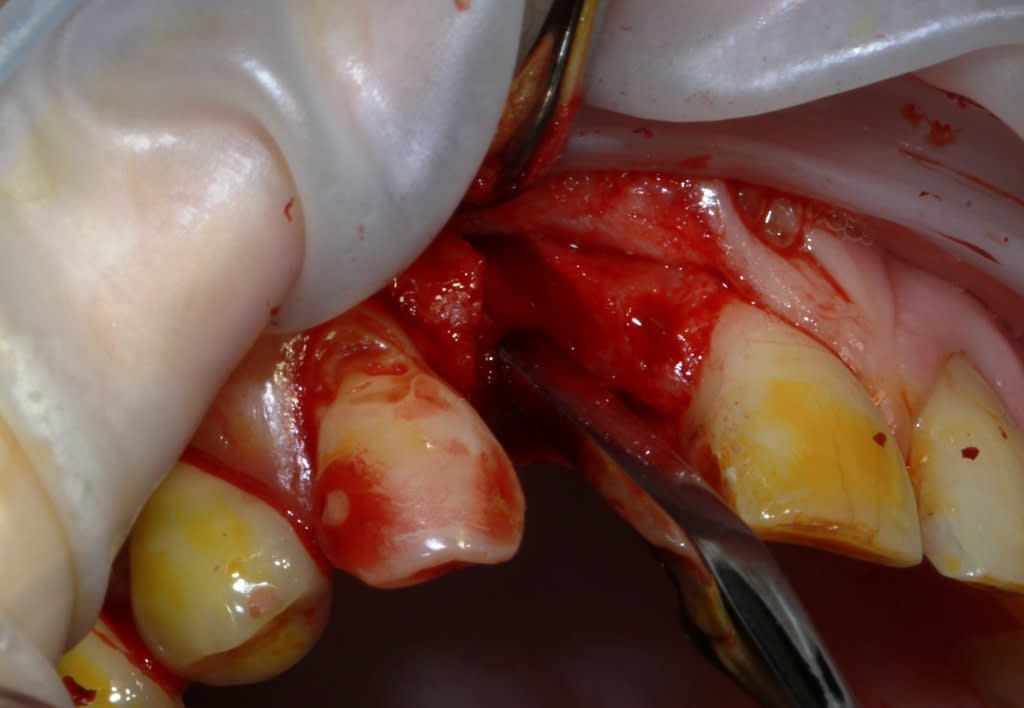

Thomas, tu as un plan pour guider dans un cas comme ça?

ou comment remplacer 12 avec soucis vestibulaire, par un implant, sans greffe, sans ROG, juste avec les mimines....?

vue de l’intérieur..